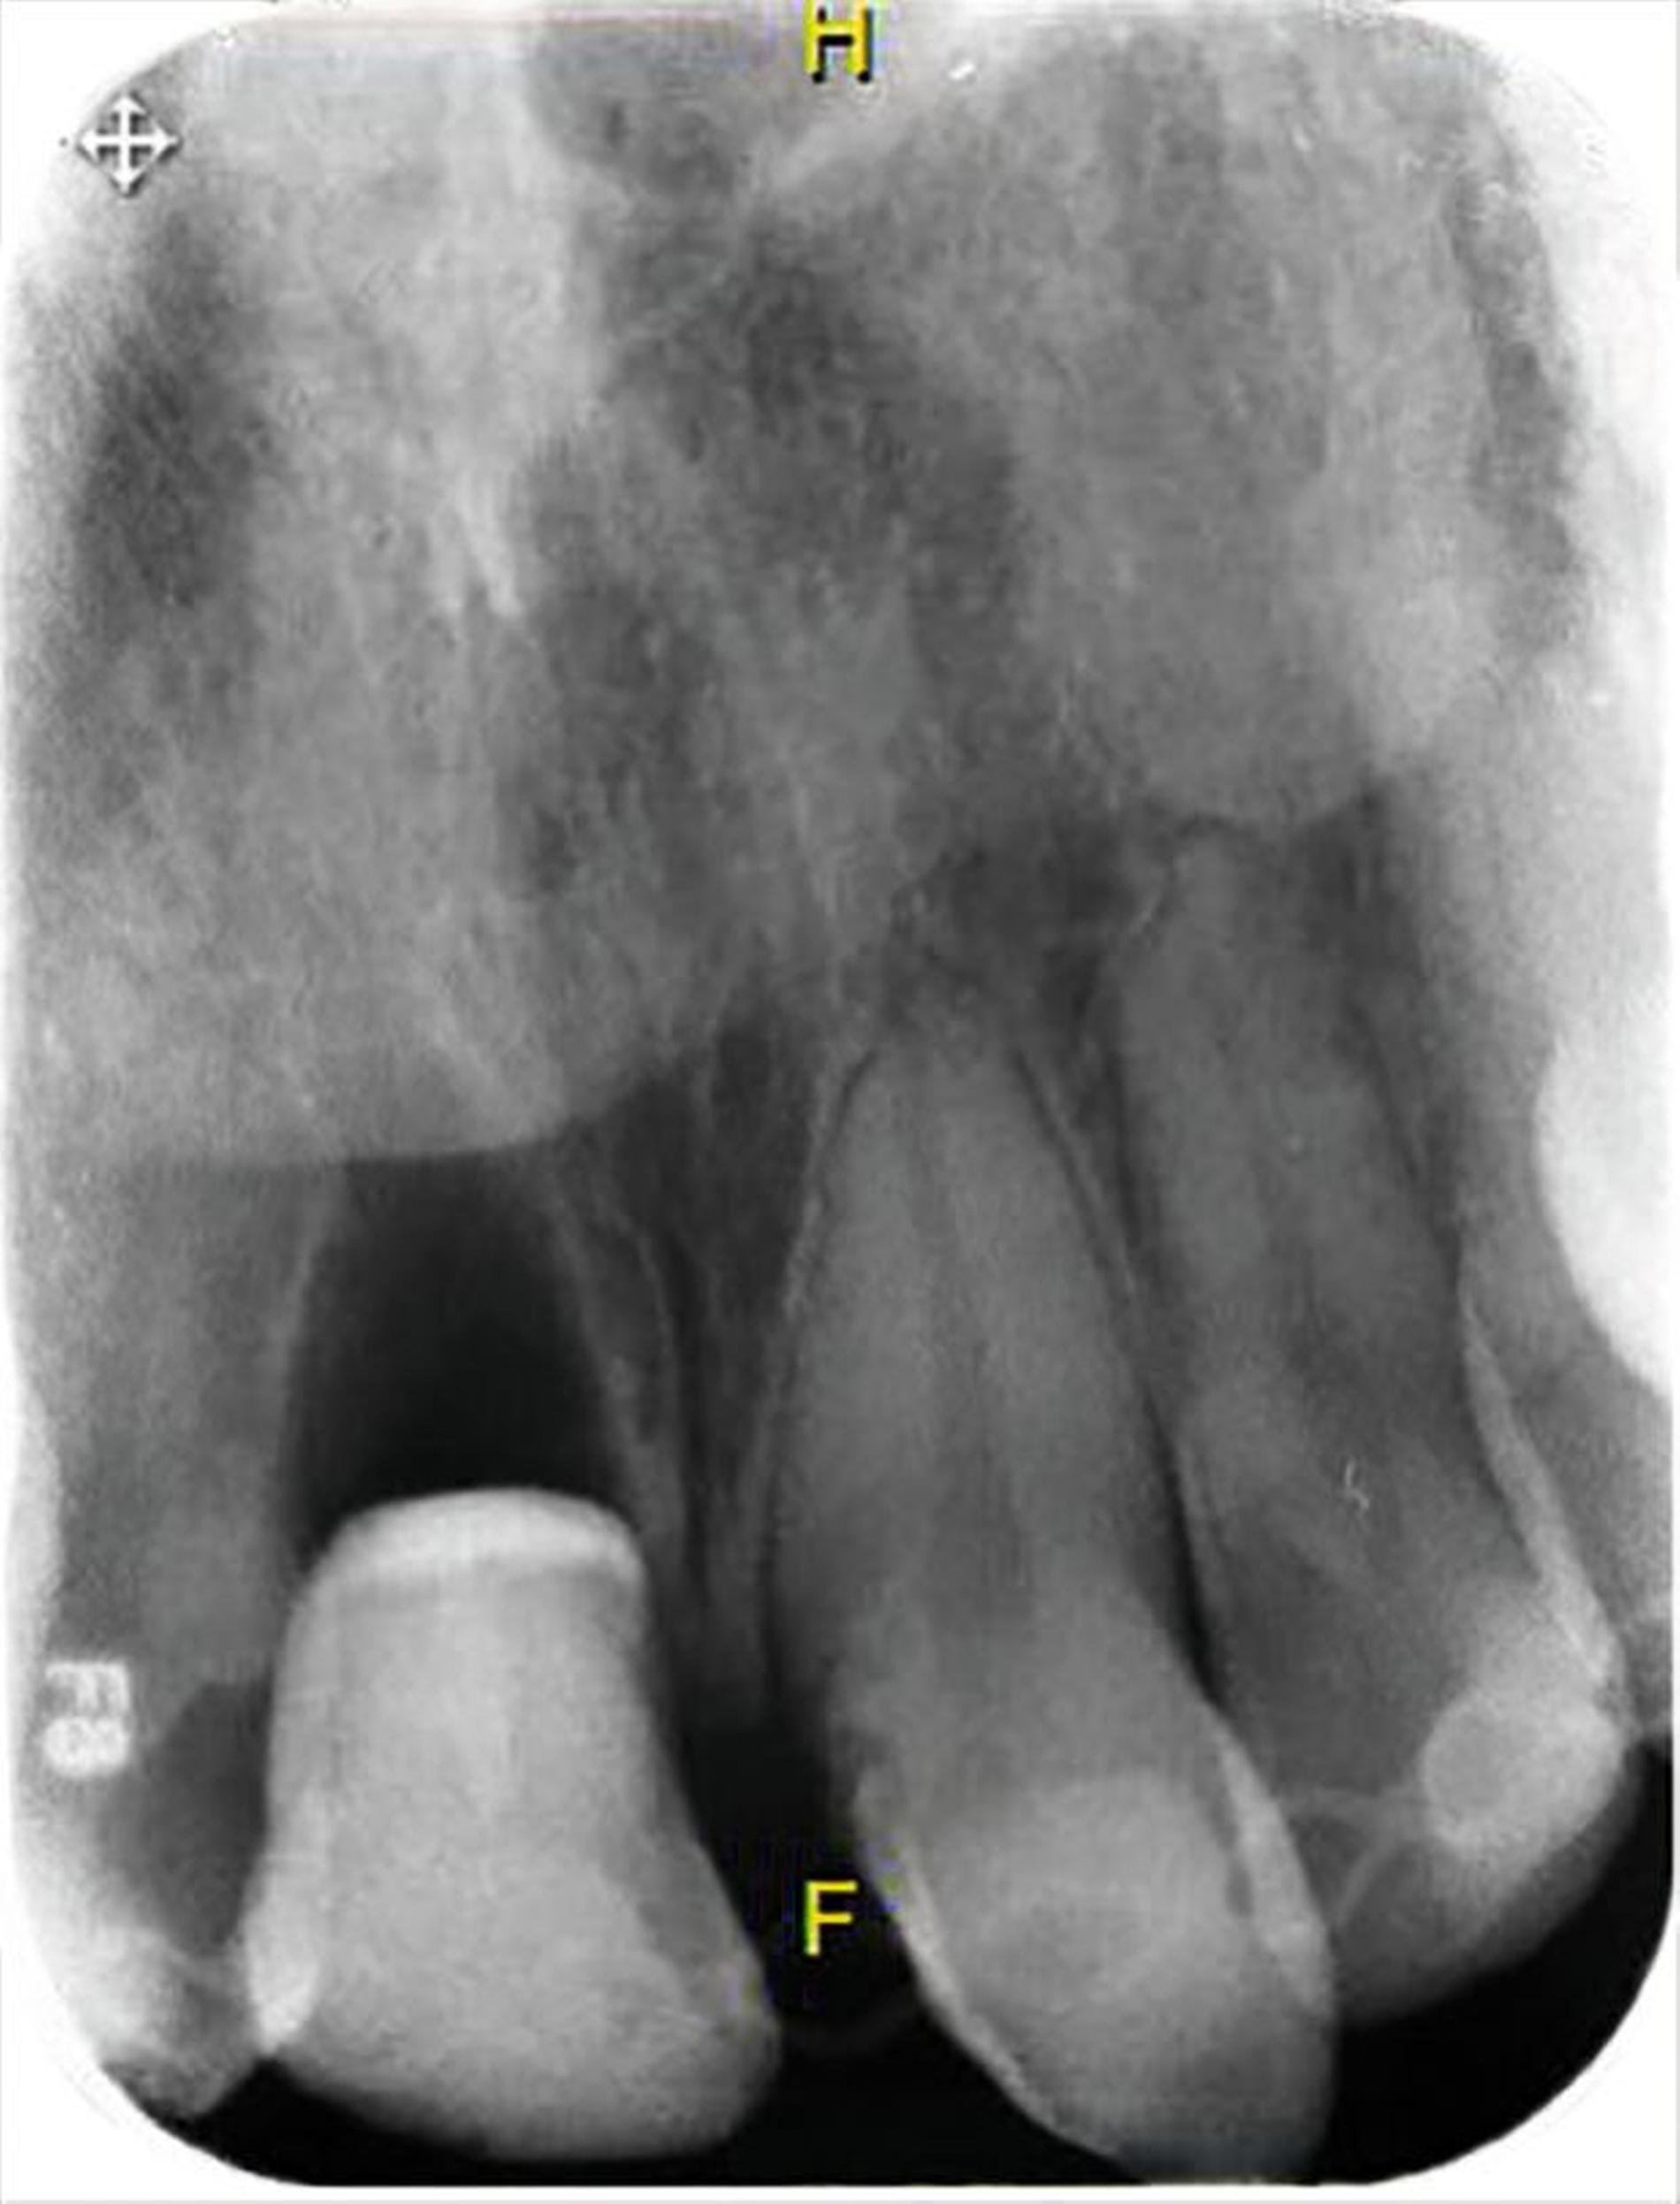

Im Fall von Kronen-Wurzel-Frakturen ist die adhäsive Fragmentbefestigung auch empfehlenswert, sofern die Fraktur suprakrestal verläuft und durch Elektrotomie oder Aufklappung suffiziente Bedingungen für adhäsive Maßnahmen geschaffen werden können. Gleichzeitig müssen zusätzliche kleinere Frakturen, die sich oftmals im palatinal-zervikalen Bereich der Wurzel befinden, ausgeschlossen werden. Die Datenlage zur klinischen Bewährung ist überschaubar. Studien zeigen sehr gute Ergebnisse innerhalb der ersten zwei Jahre [Eichelsbacher et al., 2009], aber auch erhöhte Komplikationsraten und einen negativen Einfluss auf die parodontale Gesundheit der versorgten Zähne nach einem Beobachtungszeitraum von acht Jahren [Soliman et al., 2020].

Bei tief subgingival beziehungsweise intraossär verlaufenden Kronen-Wurzel-Frakturen, deren Versorgung mit den beschriebenen Verfahren nicht möglich erscheint, können vorbereitende Maßnahmen die Defektgrenzen nach supragingival verlagern und damit die Restaurierbarkeit ermöglichen. In Einzelfällen (steiler Frakturverlauf) kann bei Kronen-Wurzel-Frakturen als Kompromiss auf eine komplette Fassung der ursprünglichen Defektgrenzen durch die Restauration verzichtet werden mit dem Ziel, invasivere Therapieoptionen zu vermeiden.

Die chirurgische Kronenverlängerung ist aufgrund der notwendigen Ostektomie das invasivste Verfahren zur restaurativen Versorgung tief frakturierter Zähne. In ästhetisch nicht relevanten Bereichen (zum Beispiel palatinal in der Oberkieferfront) kann der Defekt durch eine gezielte chirurgische Kronenverlängerung für die nachfolgende Restauration zugänglich gemacht und gleichzeitig die biologische Breite wiederhergestellt werden. Als Nachteile werden Rezidive [Pilalas et al., 2016] sowie eine mögliche Beeinträchtigung der Ästhetik am therapierten Zahn und an den Nachbarzähnen [Nobre et al., 2017] beschrieben.

Alternativ dazu bietet sich die Koronalverlagerung der Defektgrenze mit gleichzeitiger Wiederherstellung der biologischen Breite durch eine kieferorthopädische (siehe Teil 5 der Fortbildung „Dentales Trauma“: Kieferorthopädische Aspekte) oder die chirurgische Extrusion an (Abbildung 2).